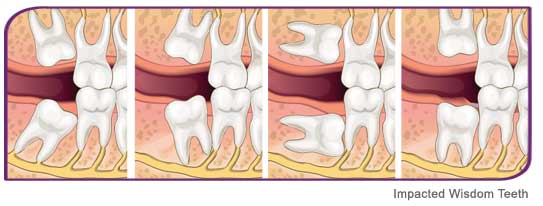

Wisdom teeth / Third molars

Wisdom teeth (your third molars) are the last teeth to come in and the ones least needed for good oral health. In most cases they may do more harm than good.

Understanding your wisdom teeth

Wisdom teeth erupt between the age of 17-25. When a wisdom tooth does not have enough space to erupt,it gets trapped in the bone.Most people have four wisdom teeth, one in each corner of the mouth.

Being at the back of the mouth,good oral hygiene remains a challenge.Thus the teeth are more prone to infection.Because of their position and angulation,wisdom teeth can cause pressure on adjacent teeth.

Complications caused by wisdom teeth

- Infection in the wisdom tooth or adjacent tooth

- Pain over the angle of the jaw

- Swelling

- Inflammed or swollen gums over the affected area

- Pressure on adjacent teeth leading to crowding

Diagnosis and treatment

- X-rays: Helps to determine position and angulation of the tooth,along with the shape of its roots.

- Medication: Antibiotics and anti- inflammatory drugs are given.

- Surgery:

- Operculectomy: If the tooth is in the right position and in the process of erupting, the flap of the gum over the teeth can be trimmed to facilitate eruption.

- Disimpaction: If the tooth is infected or if there is insufficient space for eruption, then the tooth is surgically removed